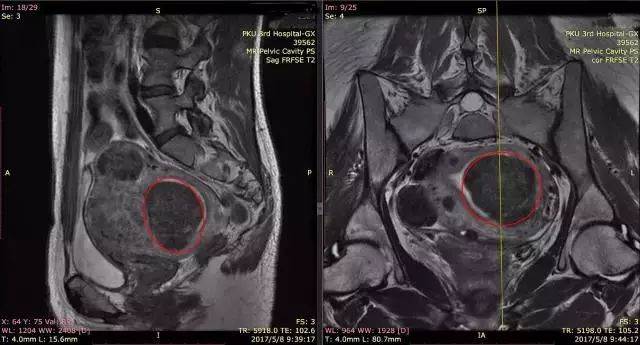

术前的磁共振显示的子宫内的多发肌瘤

子宫肌瘤为何要做核磁共振检查?